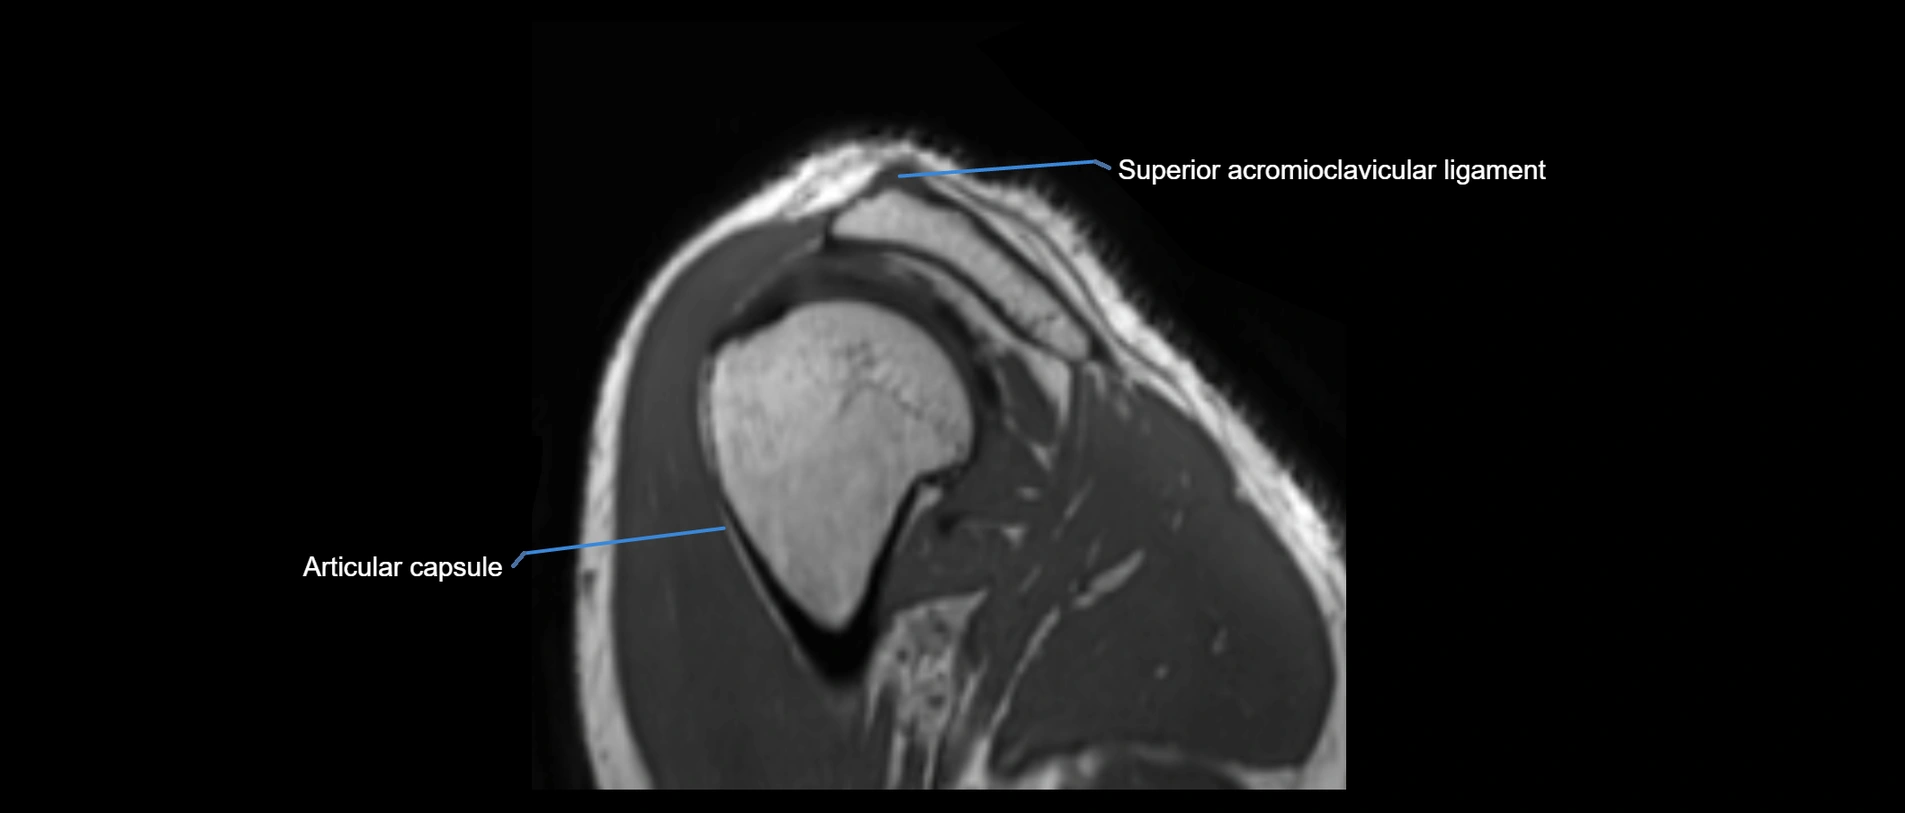

MRI images

image

MRI Appearance

• T1-weighted images:

• Normal ligament: Low signal (dark linear band) spanning acromion to clavicle.

• Surrounding fat planes: Bright, delineating the ligament clearly.

• Marrow of clavicle and acromion: Bright due to fatty content.

• Tears: Discontinuity or irregular thickening with intermediate-to-bright signal.

• Chronic injury: Thinning, fraying, or irregular low-signal fibers with adjacent scarring.

• T2-weighted images:

• Normal ligament: Low signal, homogeneous.

• Partial tear or sprain: Focal hyperintensity or thickening.

• Complete tear: Discontinuity with fluid-bright gap between clavicle and acromion.

• Associated edema: Bright signal in distal clavicle or acromion marrow.